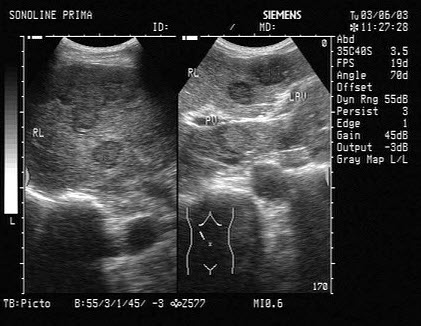

203、单项选择题

男,有高血压病史,腰部触及包块,超声检查如图所示,最可能的诊断是()

A.肾重度积水

B.多发性肾囊肿

C.多囊肾

D.肾多囊性发育异常

E.肾脓肿